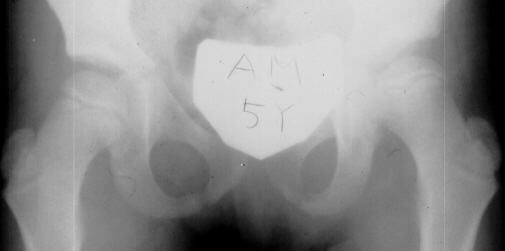

The progression of the hip is documented by x-rays taken at 1 year of age, 2 years of age, 3 years of

age, 5 years of age, 7 years of age, then at ten years of age, early closure of the lateral portion of proximal growth plate observed. Coxa valga was also observed.

The initial changes in the ossific center may follow exactly those seen in Group I, but in addition there is damage to the lateral part of the physis. The early roentgenographic signs indicating lateral physeal damage are: (1) lateral ossification, (2) lateral physeal irregularity and bridging, (3) lateral notching of the epiphysis, and (4) a lateral metaphyseal defect. The damage to the physis may remain dormant. By the age of ten years, however, valgus deformity of the head on the neck develops.( This type occurred in 35% of total AVN at AIDI.)